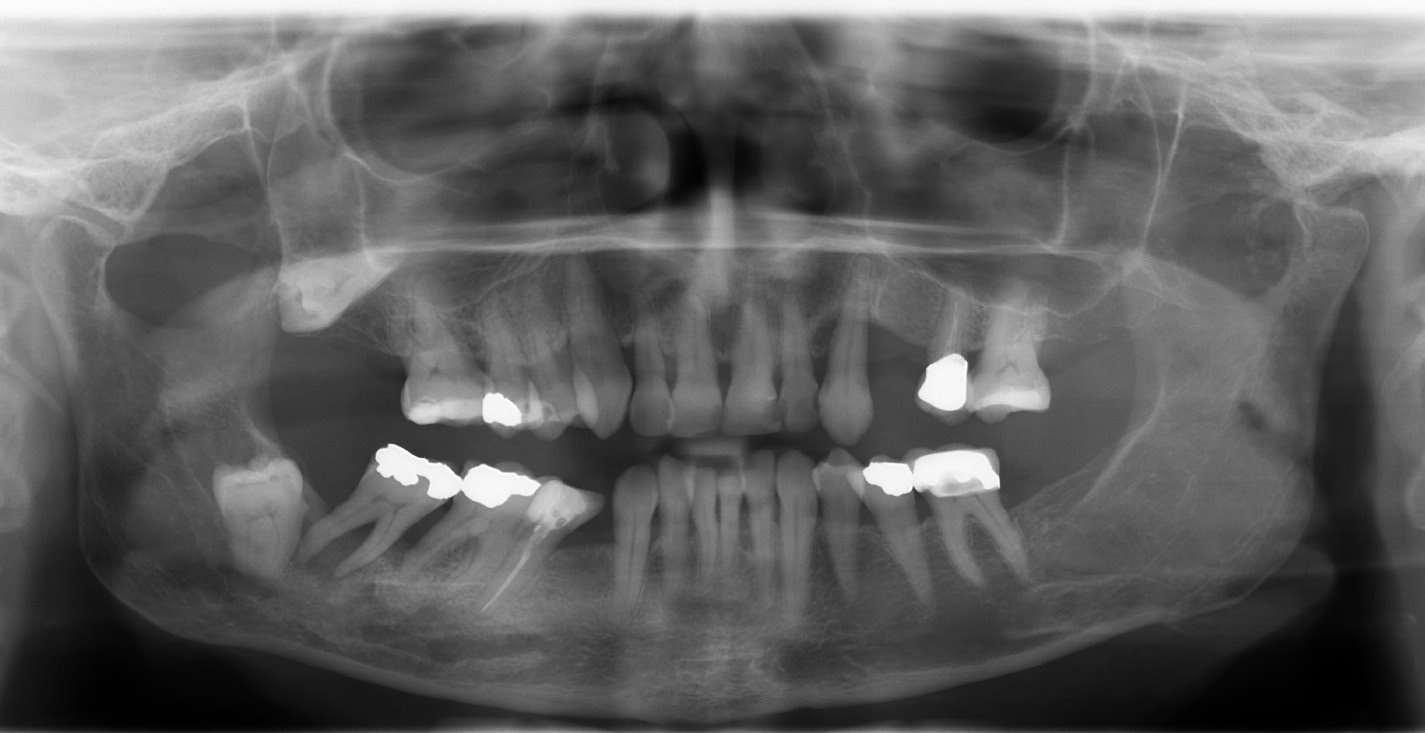

Everything you need to know about dental xrays from 123Dentist

Panoramic Dental XRay Procedure EXPLAINED PANORAMIC XRAY Panoramic Dental X Ray Contraindications Explore videos, faqs, and charts that compare radiation levels, debunk myths, and highlight the benefits. That’s why you shouldn’t have x. Be aware of their state’s laws and regulations which set specific requirements for the use of ionizing radiation. The ada encourages dentists to: As the dangers of ionizing radiation became evident, researchers and healthcare professionals have worked to minimize. Dental X Ray Contraindications.

Types of dental xrays OPG The Happy Tooth Singleton Dental X Ray Contraindications Radiographs are considered safe for the pregnant patient, at any stage during pregnancy, when abdominal and thyroid shielding is used. That’s why you shouldn’t have x. Be aware of their state’s laws and regulations which set specific requirements for the use of ionizing radiation. Explore videos, faqs, and charts that compare radiation levels, debunk myths, and highlight the benefits. The. Dental X Ray Contraindications.

OPG XRay Get Price, Purpose, Results & Sample Report [2024] Dental X Ray Contraindications The ada encourages dentists to: Explore videos, faqs, and charts that compare radiation levels, debunk myths, and highlight the benefits. Be aware of their state’s laws and regulations which set specific requirements for the use of ionizing radiation. As the dangers of ionizing radiation became evident, researchers and healthcare professionals have worked to minimize these. That’s why you shouldn’t have. Dental X Ray Contraindications.

When do you need an OPG or full mouth Xray? Dental Blog Dental X Ray Contraindications Radiographs are considered safe for the pregnant patient, at any stage during pregnancy, when abdominal and thyroid shielding is used. Be aware of their state’s laws and regulations which set specific requirements for the use of ionizing radiation. Explore videos, faqs, and charts that compare radiation levels, debunk myths, and highlight the benefits. That’s why you shouldn’t have x. The. Dental X Ray Contraindications.